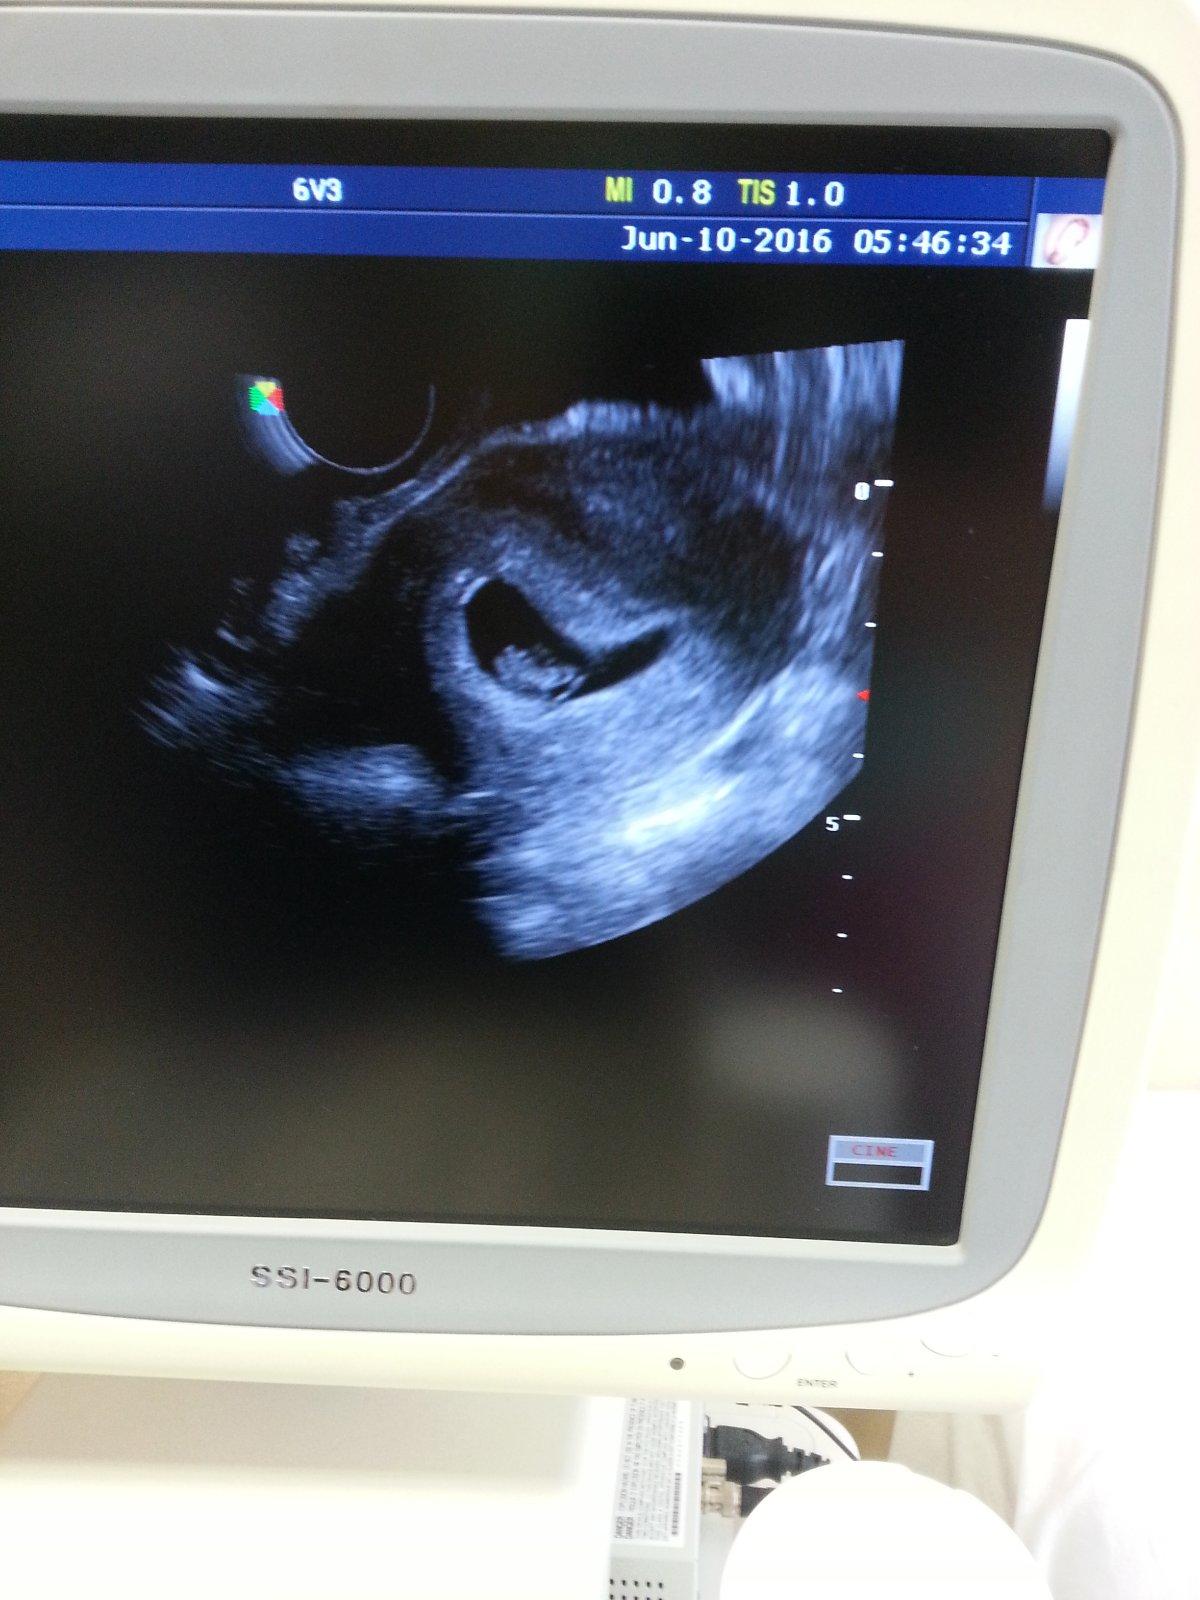

@madarka123 Tesiiiim sa s tebou. Gratulujem. Srdiecko bije?

@meli8412 noo a ešte ako 🙂

@madarka123 To je suproveeee. Krasne tehulkovanie so stastnym koncom